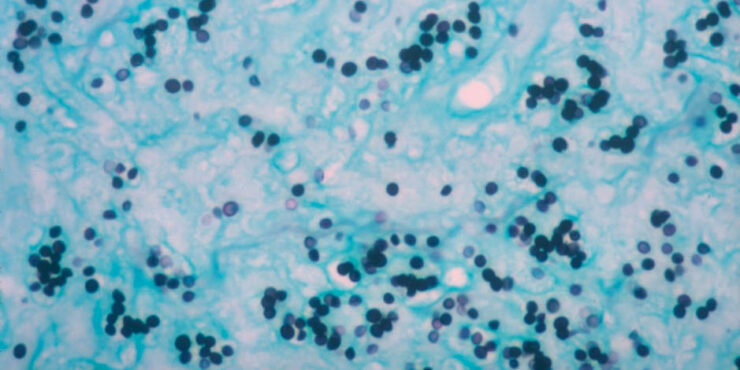

Read MoreHydroa vacciniforme =المائية اللقاحينية Hydroa Vacciniforme HV is a very rare, intermittent, UVR-induced, blistering, scarring eruption of only some exposed skin, usually in children and only rarely in adults . The condition generally has onset by 10 years of age, with resolution by early adulthood. Usually sparse, occasionally coalescent, symmetrically scattered, sometimes hemorrhagic vesicles and […]